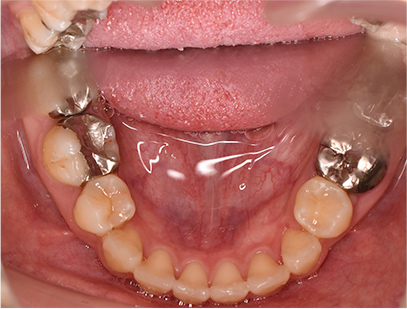

• 上側

• 下側